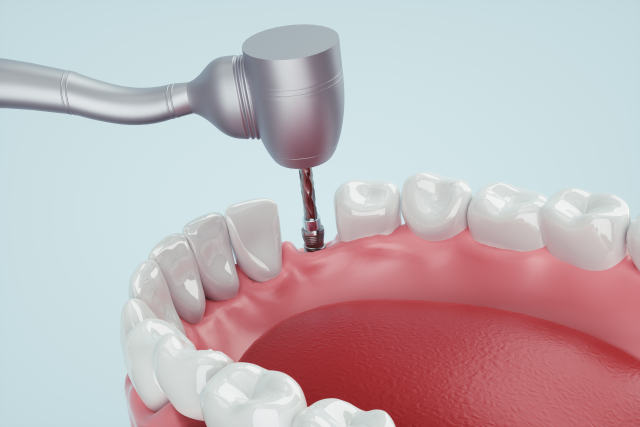

03.

手術用ガイドを用いた手術

シュミュレーションした位置に正確にインプラントが埋め込めるように、マウスピース型の手術ガイドを作成します。このガイドを使用して手術を行うことで、事前にシュミュレーションした位置にピンポイントでインプラントを埋め込むことが可能です。このガイドを使わず手術をしていた頃は、インプラントを埋め込む方向や深さを注意深く何度も確認しながら手術を進めるため手術時間も現在より長くかかっていました。そういった意味ではこのガイドの存在により手術を短時間で終えることもでき、患者さんにとって負担の少ない手術を実現していると言えます。